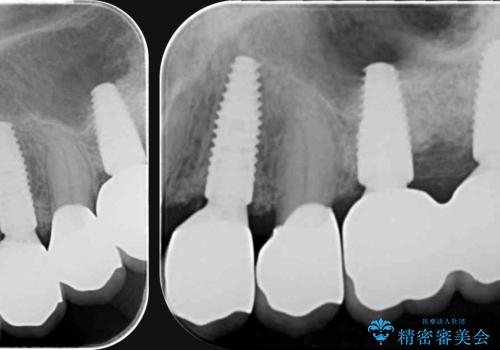

インプラント・ブリッジ補綴を含む、歯周病全顎治療

全体的な歯周病検査を行い、多数の残すことのできない抜歯の必要な歯を認めたため、残せる歯に対しての徹底的な歯周病治療、失った歯に対しブリッジ・インプラント治療を全顎的に行っていくこととしました。

長期間にわたる治療後、歯に対する意識も大きく変わりプラークコントロールも非常に良くなりました。

数ヶ月に一度のチェックをしっかりと行い、ブリッジ・インプラントが長期間使用できるようメンテンスを行っていきます。